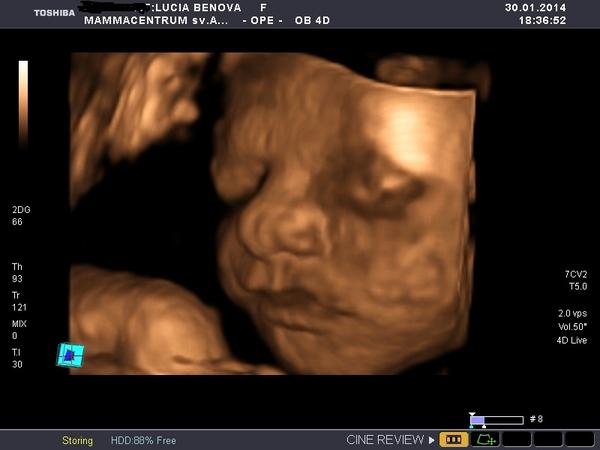

moja vážila 1660g - foto dole z 3d v tom tyzdni a narodila sa ako 53cm a 3470g 🙂 4 dni pred termínom. Nestrachuj sa nemáš čoho, sono je len odhad a veľakrát nie presný, mne v porodnici povedal primar ze je malinka a aha🙂 bola mišelinko 🙂 a to mi povedal 5 hodin pred porodom 😀 a ďalší fakt od 32 tt začnu deti len rast a priberat dovtedy sa aj vyvyjaju rozne veci v nich 🙂 🙂